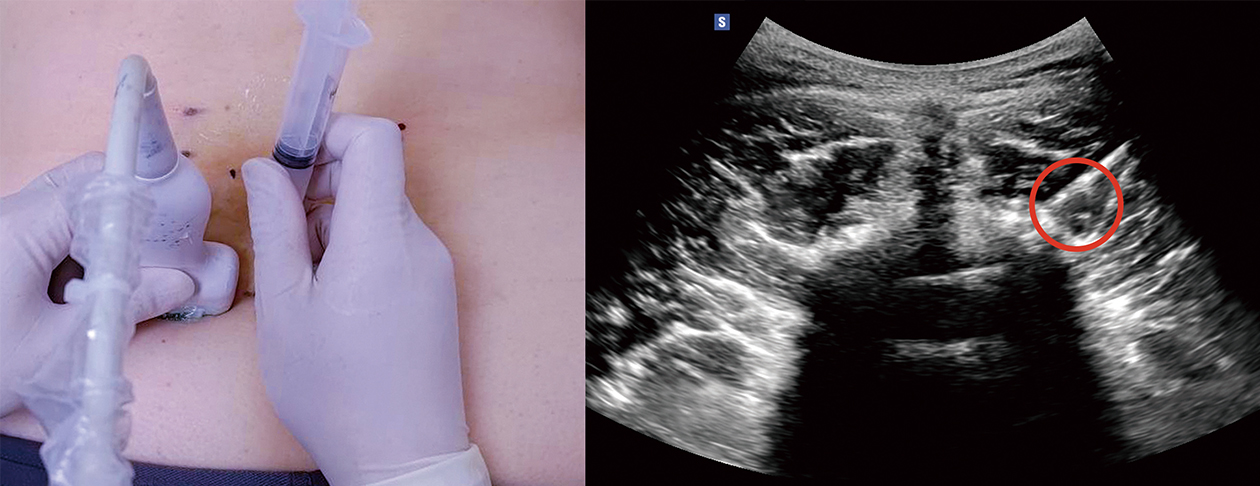

所謂介入性疼痛治療,就是在X光或超音波的協助下,精確地將針放到病灶處,標靶式使用高頻電刺激調控引起疼痛之病變神經,或利用溫度破壞可能引發疼痛的病灶而得以快速達到緩解疼痛的目標。一般而言,一個療程可能會需一至三次治療才成完成。相較於一般手術,介入性疼痛治療的傷口僅有幾個針孔,不需特殊傷口照護,建議手術後4-6 小時不要碰水,隔天即可正常生活及工作。介入性疼痛治療有著低風險、治療時間短、不需全身麻醉的優點。

• 圖二 利用超音波引導定位病灶與進行神經阻斷術

• 圖三 手術即時影像定位病灶